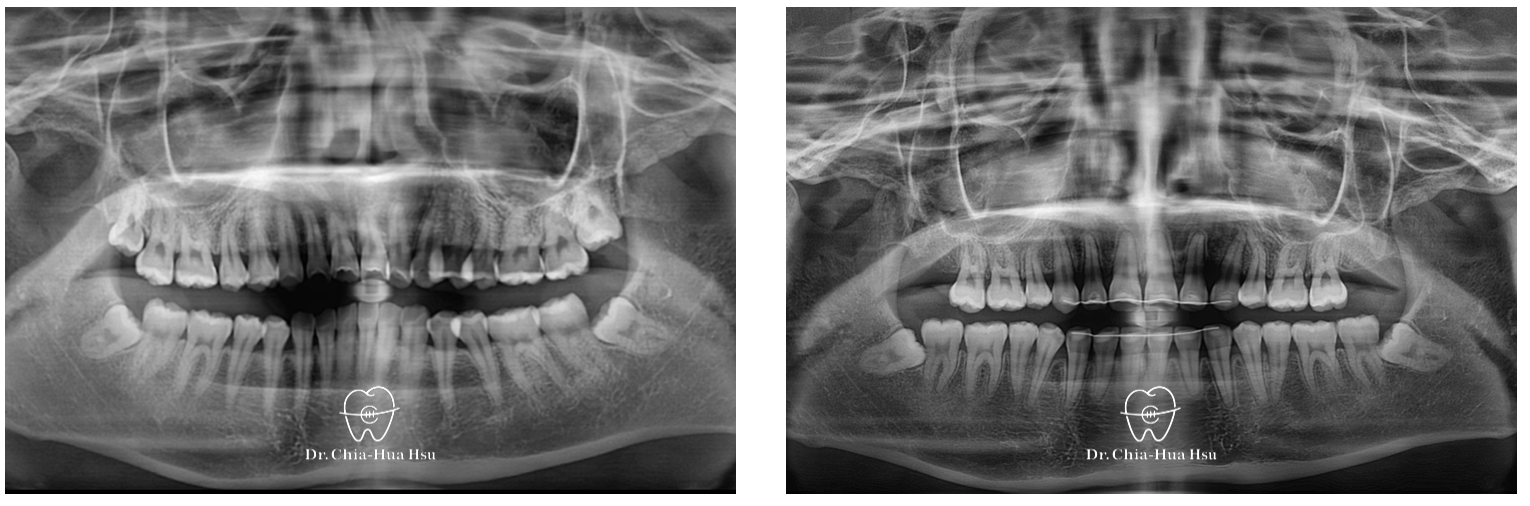

• 病患主訴:暴牙、嘴凸、深咬。

• 問題分析:患者是牙齒二類咬合(Skeletal Class II)、方臉型、暴牙以及齒列不整齊。

• 治療方式:使用傳統金屬矯正器,考量到患者臉型不適合退太多,因此只拔除上顆兩顆小臼齒以及兩支暫時性迷你骨釘來完成治療。

• 治療時間:2 年 7 個月。

• 治療結果:齒列排齊,嘴凸改善,外觀變得更和諧,笑容也更有自信。